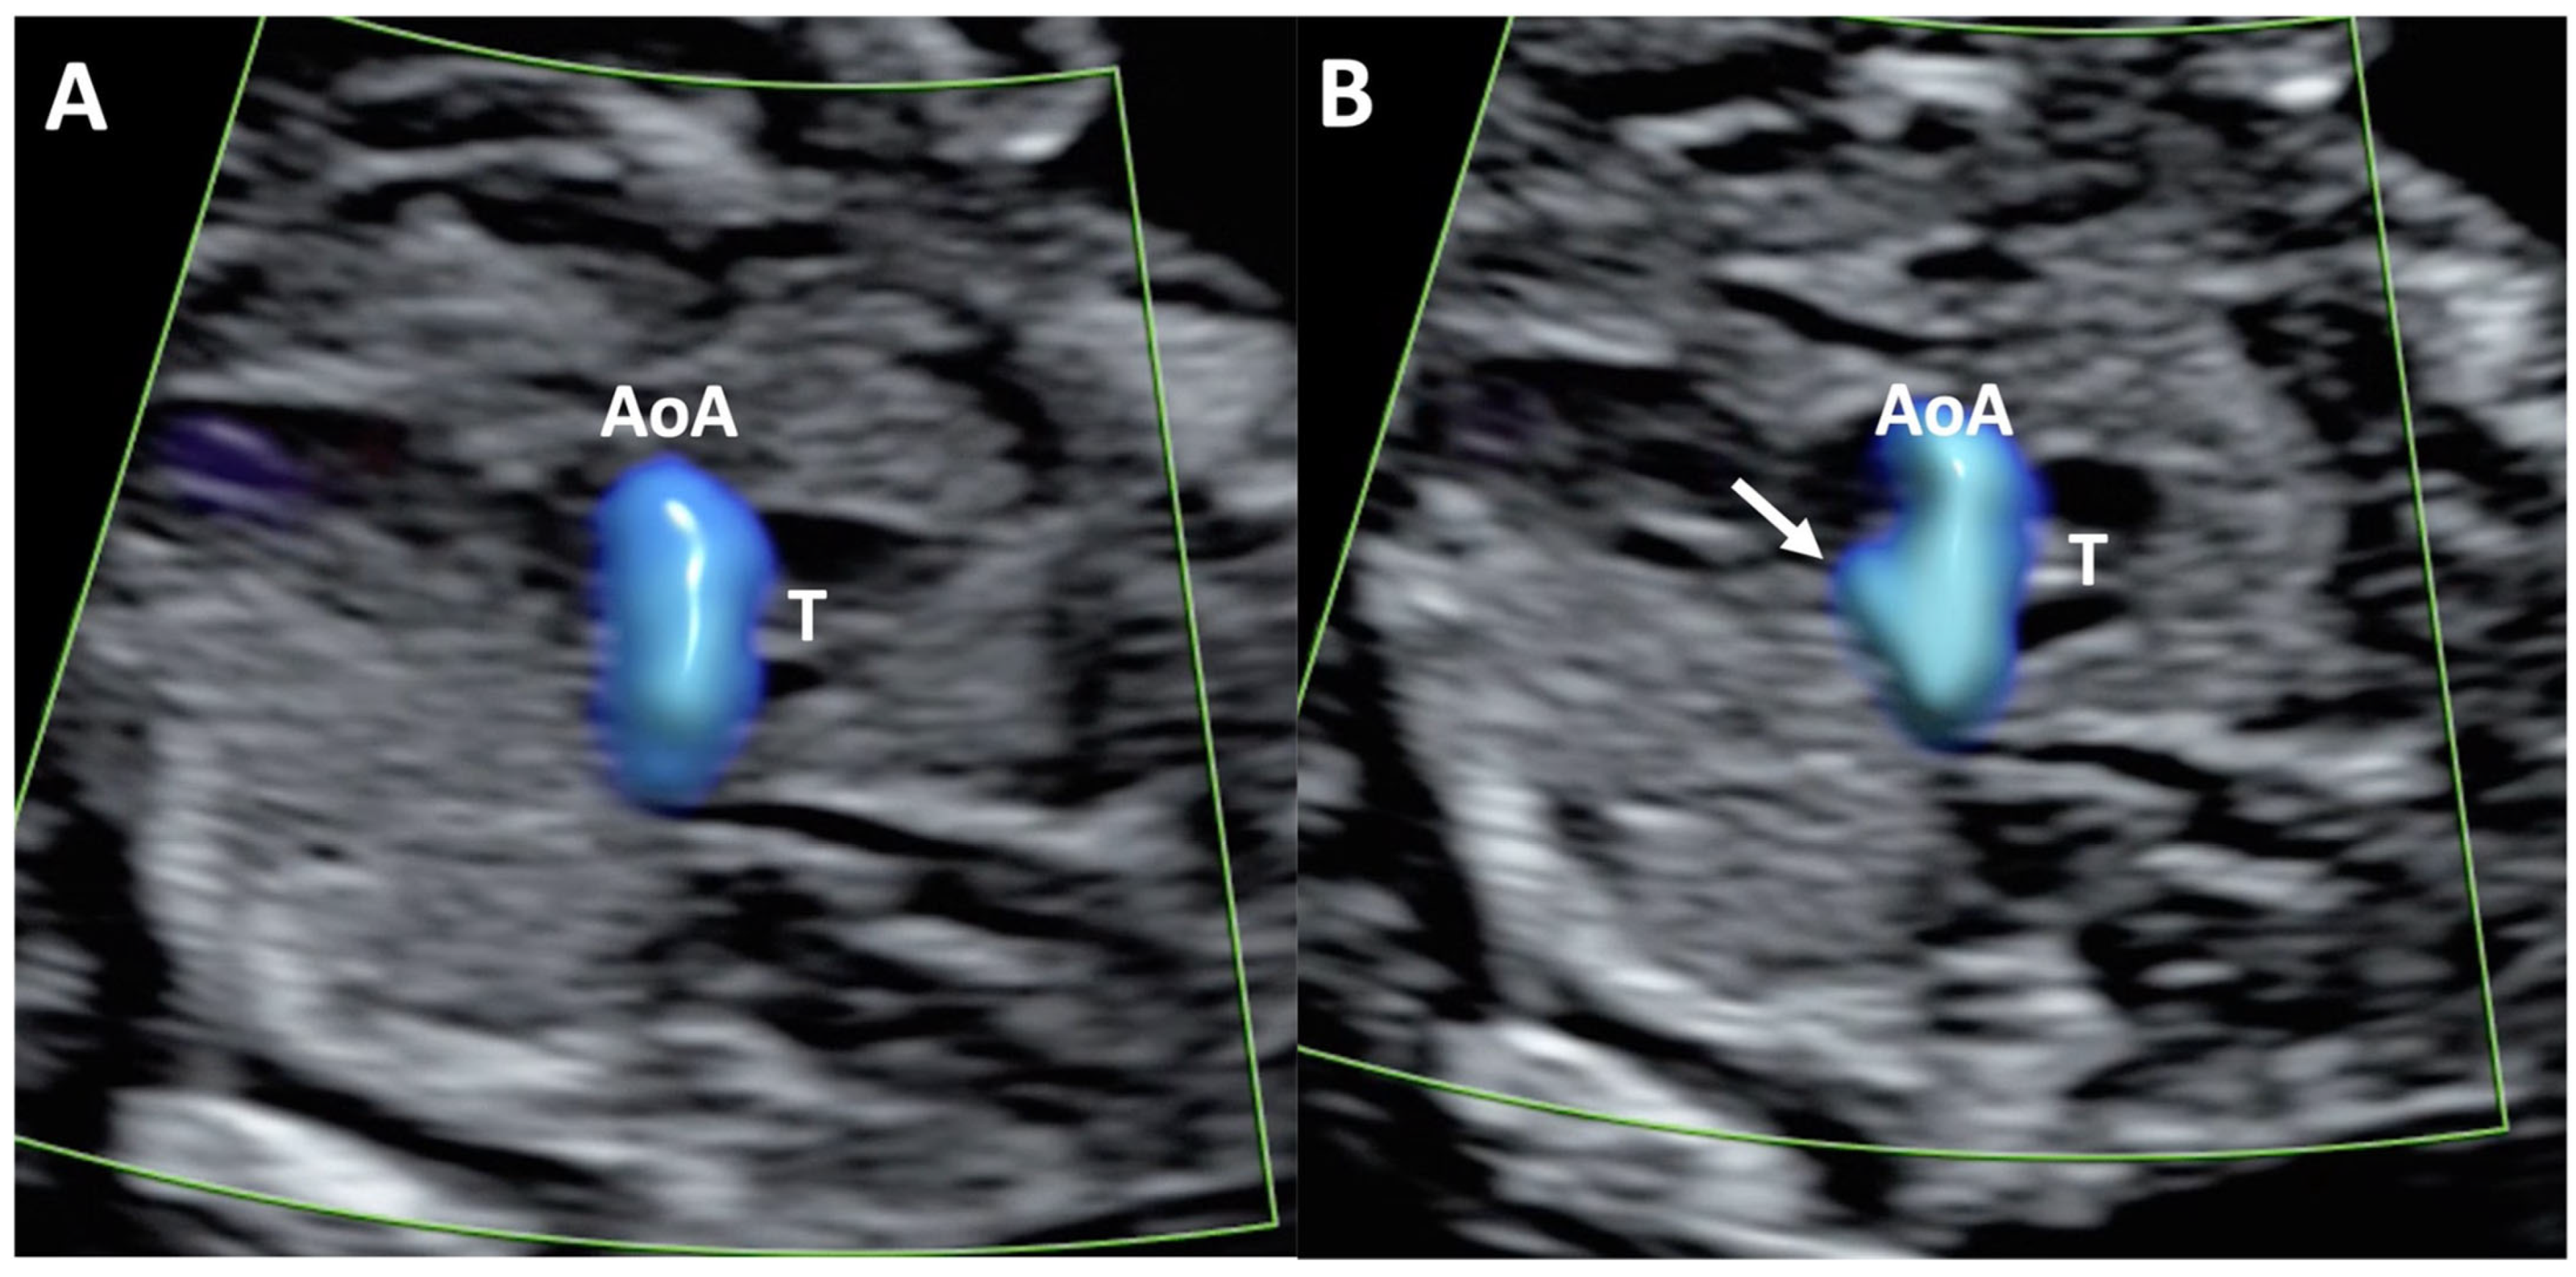

Inter-Operator Color Doppler Pattern Identification Agreement

Overall, the analysis demonstrated an almost perfect agreement in the assessment of the total 90 included cases for both the 4CV and the 3VTV planes (K between 0.84 and 0.97) between the two operators and between each operator and the fetal cardiologist. The two operators showed a perfect agreement (K = 1) on the evaluation of the 4CV and 3VTV in the control group. Different levels of agreement were observed on the color Doppler pattern assessment in fetuses with CHD. Indeed, in this subgroup, the agreement between the operators and between each of them with the fetal cardiologist was almost perfect on the evaluation of the 4CV plane. Conversely, for the 3VTV, a lower agreement level was reported between the operators and with the fetal cardiologist (i.e., substantial agreement, K between 0.77 and 0.80). We additionally performed a sub-analysis to evaluate the inter-operator agreement in the assessment of each specific color Doppler pattern. Details regarding operators and fetal cardiologist pattern-specific agreement are displayed in Table 2. An almost perfect agreement was observed between operators 1 and 2, as well as between both operators and the fetal cardiologist, for pattern 1 (“two A-V inflows of similar size”) and pattern 3 (“one A-V inflow with filling of one ventricle”) of the 4CV, and for pattern 1 (“normal V sign”) of the 3VTV. The 4C pattern in which we observed the lowest agreement between operators and with fetal cardiologist was “two A-V inflows with ventricular disproportion” (50% agreement), while the lowest agreement on the assessment of 3VTV was reported for abnormalities “in the number” and “in the dimension” of the vessels (agreement ranging from 40% to 77.8%) (Figure 1). The overall mean K coefficient for intra-operator agreement was 0.87 with an interquartile range of 0.128, confirming good intra-operator agreement on the two views at two different times.

Figure 1.

Case of disagreement in the characterization of color Doppler pattern on the 3VTV between operators 1 and 2 in a case of Ebstein anomaly at 12 + 6 weeks’ gestation. (A,B) show different frames of a videoclip of the 3VTV. (A) Operator 1 observed an abnormal 3VTV pattern in terms of “abnormal vessel number”; (B) operator 2 characterized the same case as with “abnormal vessel dimensions”. AoA, aortich arch; T, trachea; arrow, small pulmonary artery.

To the best of our knowledge, this is the first study that aimed to assess the ability of experienced operators in recognizing normal and abnormal color Doppler patterns on the 4CV and 3VTV of the fetal heart in the first trimester of pregnancy. We also evaluated how the operators performed compared to a fetal cardiologist, which was considered the gold standard in the evaluation of the fetal heart. We observed a perfect agreement (K = 1) between the two operators in evaluating the 4CV and 3VTV in normal cases (control group), which confirmed the high level of confidence experienced operators have in excluding the presence of CHD in normal cases. This is in line with previously published data, which showed a very high specificity (99.75%) for major CHD identification at direct first-trimester fetal heart evaluation in high-risk population [10]. However, a different agreement level was observed on the color Doppler pattern assessment in cases where a CHD was present. Indeed, in this subgroup of cases, the agreement between the operators and between each of them with the fetal cardiologist remained high (almost perfect) during 4CV plane evaluation, but it slightly dropped in the evaluation of the 3VTV. When we evaluated operators’ performance in the assessment of each specific color Doppler pattern on the 4CV, an almost perfect or substantial agreement was observed between operators and with the fetal cardiologist for all patterns, with the exception of pattern 4, which corresponded to ventricular disproportion. For this pattern, a significant discrepancy was observed in the level of agreement between operator 1 and operator 2 with the fetal cardiologist (Table 2). This inconsistency could be attributed to the limitations in subjectively perceiving the size difference between the two-color signals passing through the A-V valves at gestational ages, where the fetal dimension represents a challenge in the evaluation of anatomical structure, particularly the heart. This aspect might also account for the low level of agreement recorded in the assessment of number or dimension abnormalities on the 3VTV (patterns 2 and 3) (Table 2). Indeed, these signs are very subtle and hard to recognize and correctly interpret during the first trimester of pregnancy. This aligns with the lower detection rate reported in the literature for cardiac anomalies characterized by these abnormal findings on the 4CV and 3VTV (i.e., 4CV pattern 4 and 3VTV patterns 2 and 3) [29,30], such as coarctation of the aortic arch, pulmonary and aortic valve stenosis, and conotruncal anomalies [10]. In fact, for these groups of CHD, the reported detection rate in the literature ranges between 25% and 60% [10], which is significantly lower than the rate reported for univentricular heart, A-V septal defects, and complex cardiac defects (>60%) [10]. Operator expertise in correctly recognizing and interpreting the abnormal color Doppler signs displayed on the screen is pivotal in making the correct diagnostic process, and human error at this task has been demonstrated to be one of the most common causes of false-negative results in the first-trimester assessment of the fetal heart [26,31]. While our findings suggest that specific Color Doppler flow patterns can support the early identification of CHD, particularly in cases of univentricular heart, their diagnostic value may be limited in cases with subtle ventricular disproportions or subtle abnormalities visible only in the three vessels–trachea view. This underscores the importance of prospective studies to further validate these observations and refine their clinical applicability.